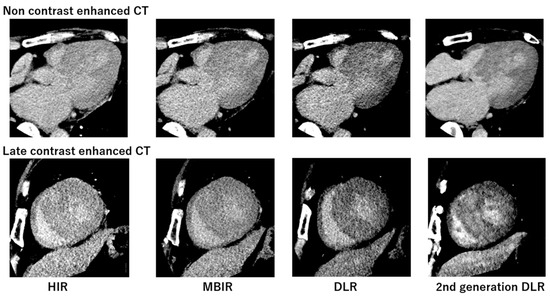

3.3. Comparison of Synthetic ECV and Laboratory ECV across Four Reconstruction Methods in the Validation Cohort